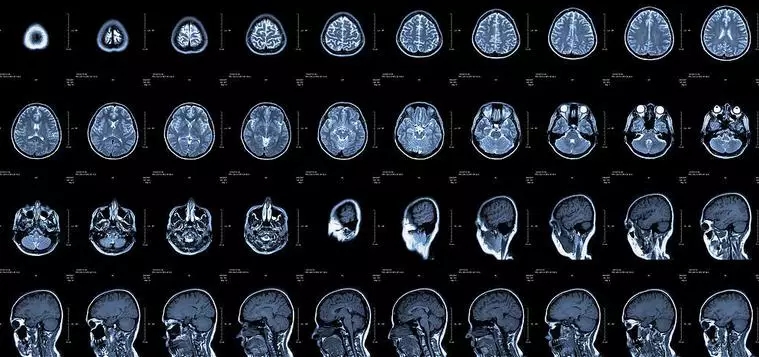

核磁共振:摇一摇再看

0.webp (2).jpg

核磁共振机使用较强大的磁场,使人体中所有水分子磁场的磁力线方向一致,这时磁共振机的磁场突然消失,身体中水分子的磁力线方向,突然恢复到原来随意排列的状态。简单说就相当于用手摇一摇,让水分子振动起来,再平静下来,感受一下里面的振动。所以,核磁共振(MRI)也被戏说为是摇摇看的检查。